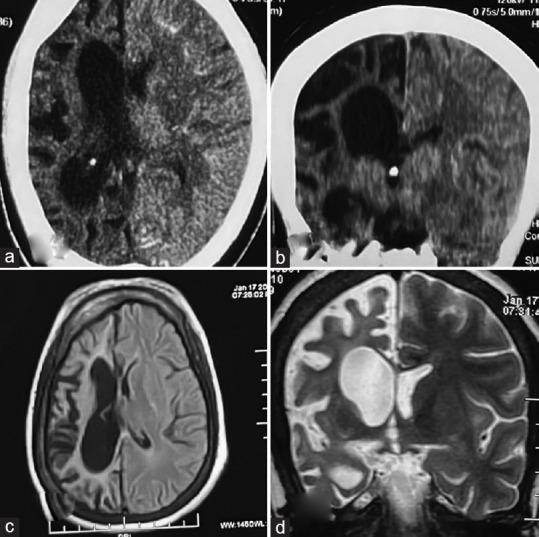

Dyke-Davidoff-Masson syndrome (DDMS) is a rare neuro-osteal syndrome of childhood and a constellation of cerebral hemiatrophy, facial asymmetry, seizures, osseous changes, and hemiplegia. It commonly presents with seizures and hemiplegia. The involvement of the kidney in DDMS is not known in the available literature, except in a case report that described ectopic kidney in DDMS. We present the case of a 15-year-old boy who presented with recurrent seizures, right facial palsy, left hemiparesis, and advanced renal failure. The neuroimaging revealed diffuse right cerebral atrophy, dilatation of the ipsilateral lateral ventricle, and ipsilateral thickening of the calvaria. The nephrological evaluation suggested the diagnosis of chronic kidney disease stage VD, probably secondary to congenital hypoplasia of the kidney.

戴克-戴维多夫-马森综合征(DDMS)是一种罕见的儿童神经骨综合征,表现为一系列症状,包括大脑半球萎缩、面部不对称、癫痫发作、骨质改变和偏瘫。它通常表现为癫痫发作和偏瘫。在现有文献中,除了一篇描述DDMS患者异位肾的病例报告外,肾脏在DDMS中的受累情况尚不清楚。我们报告一例15岁男孩,他出现反复发作的癫痫、右侧面神经麻痹、左侧偏瘫和晚期肾衰竭。神经影像学检查显示右侧大脑弥漫性萎缩、同侧侧脑室扩张和同侧颅骨增厚。肾脏科评估提示诊断为慢性肾脏病ⅤD期,可能继发于先天性肾发育不全。